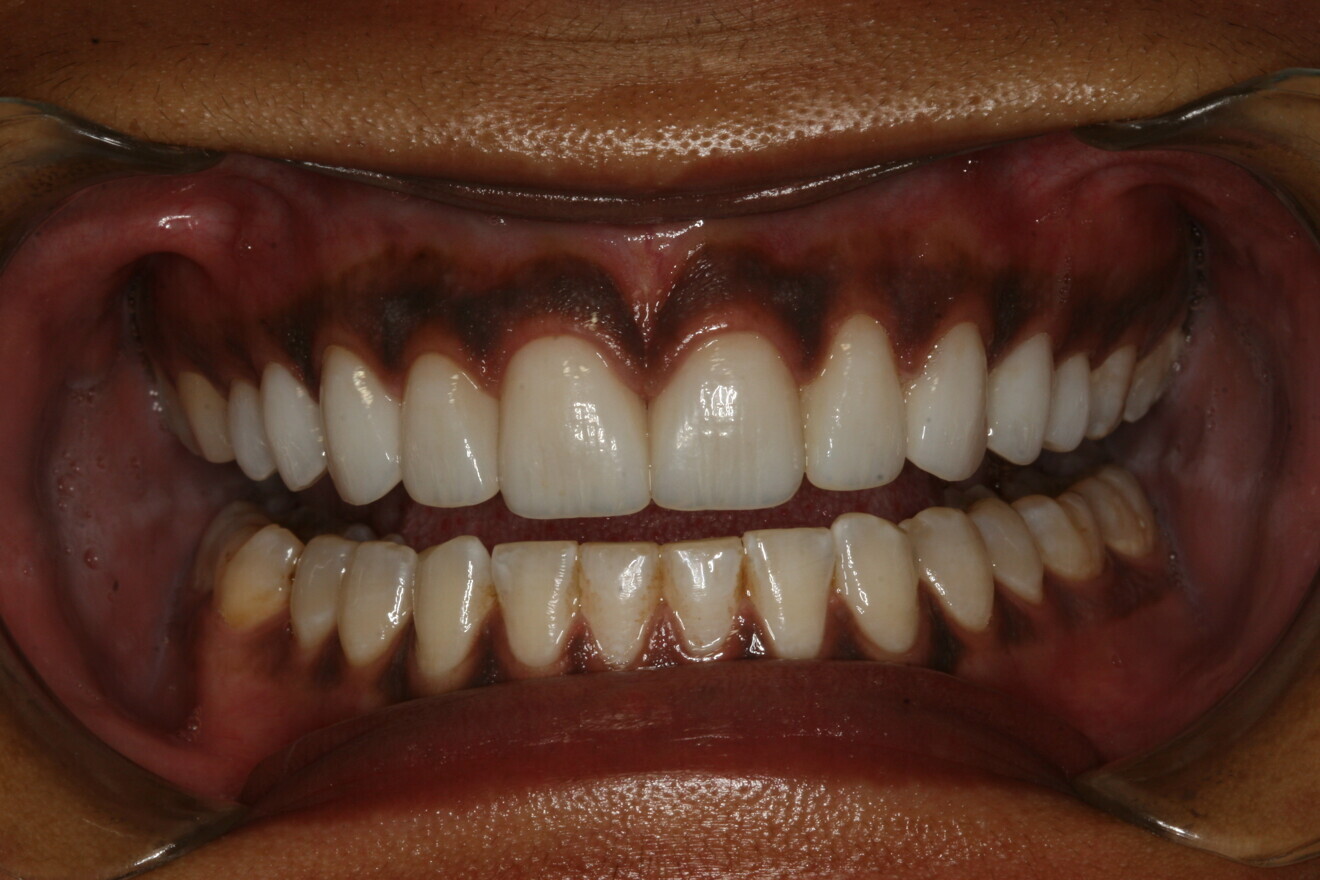

A 24-year-old female patient in excellent medical and good dental health presented stating she had not been to the dentist in some time and wished to improve her oral health and the appearance of her teeth. The pa­tient was unhappy with the shape and shade of her teeth. She was particularly concerned with the im­proper proportions of the width-to-length ratios of her incisors and the diastema present between teeth #11 and 21 (Figs. 1 & 2).4 Several areas of gingival asymmetry were also noted. The patient stated that she had re­ceived orthodontic treatment in the past, and cos­metic bonding (which had already failed at the time of her presentation) to close the diastema between teeth #11 and 21. She expressed her desire to have a beautiful, brighter and natural-looking smile.

Fig. 1: Pre-op full smile.

Fig. 8: Post-op full smile.

The patient returned the following day. Her functional oc­clusion was evaluated, and her teeth were inspected for any re­sidual cement. Postoperative radiographs were taken to con­firm positive seating of the margins and the absence of any residual interproximal cement. Maxillary and mandibular alginate im­pressions were taken along with a polyvinylsiloxane bite reg­istration for fabrication of a maxillary full-arch bite guard for night-time wear.6 Postoperative home care instructions were given, and the patient was scheduled for a follow-up appoint­ment for additional photographic documentation, a final check for function and aesthetic evaluation, and delivery of the bite guard (Figs. 8 & 9).6